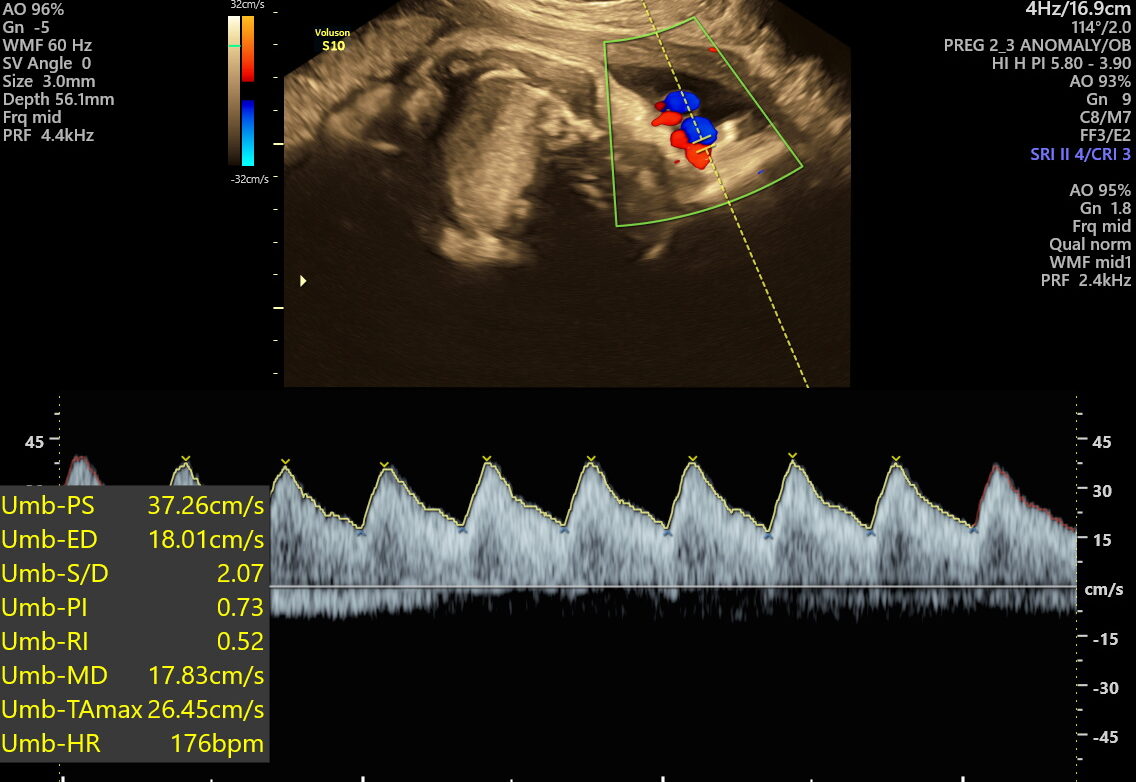

- Vital Functions: Measures movements, breathing, and heart rate to make sure your baby is thriving.

This scan focuses on confirming birth readiness and spotting sudden issues that may arise close to your due date. It includes detailed Doppler studies to check blood flow in the umbilical cord and brain, ensuring your baby gets enough oxygen and nutrients.

- Abnormal umbilical cord blood flow or cord entanglement

- Fetal distress signs